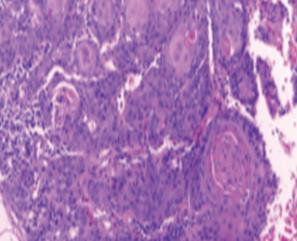

El carcinoma oral de células escamosas es la neoplasia maligna más frecuente de la cavidad oral, presentándose fundamentalmente en personas mayores de 60 años, aunque recientemente se ha observado un aumento de su incidencia en individuos jóvenes.

La etiología del carcinoma oral de células escamosas en pacientes jóvenes aún no está esclarecida, destacándose en la literatura que los factores de riesgo clásicos como el tabaco, el alcohol y la infección por el virus del Papiloma Humano, no tendrían implicancia en su etiopatogenia; siendo el microambiente tumoral la principal diferencia biológica observada entre los distintos grupos etarios.

Históricamente se consideró que el carcinoma oral de células escamosas en personas jóvenes era más agresivo, sin embargo, estudios actuales han demostrado que no existen diferencias significativas con respecto al desarrollado por personas de edad más avanzada, resaltando que el pronóstico y el plan de tratamiento no deben ser definidos en función de la edad cronológica al momento del diagnóstico, sino por el estadio de la enfermedad.